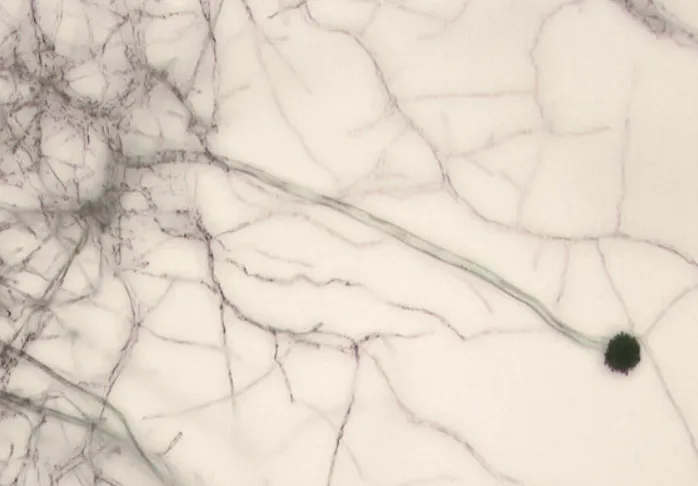

2025년 5월 2일(현지시간) 영국 맨체스터대 소속 노르만 판레인, 리버풀 열대의학대학원 소속 크리스토퍼 유젤, 영국 생태수문학센터(UKCEH) 소속 제니퍼 셸턴 등 박사후 연구원 3명이 인터넷에 공개한 아스페르길루스 균류의 지리적 이동 예상 논문 초안에 실린 지도와 그래프. 리서치스퀘어 공개 프리프린트 캡처

특히 온대지방에 흔한 ‘아스페르길루스 푸미가투스’ 종은 2100년까지 분포 지역이 77.5% 증가해, 유럽 주민 900만명이 노출될 가능성이 있는 것으로 평가됐다. 사하라 이남 아프리카 등에서는 온난화로 아스페르길루스 곰팡이류가 살 수 없게 될 가능성이 있으나, 이 경우 토양 생태계 등에 영향이 있어 또 다른 문제가 생길 수도 있다.

더운 열대 기후를 선호하는 ‘아스페르길루스 플라부스’ 종은 인간이 계속해서 많은 양의 화석 연료를 태울 경우 확산 속도가 16% 증가할 수 있다는 연구 결과가 나왔다. 이 종은 북미, 중국 북부, 러시아 일부 지역으로 확산될 것으로 예측됐다.